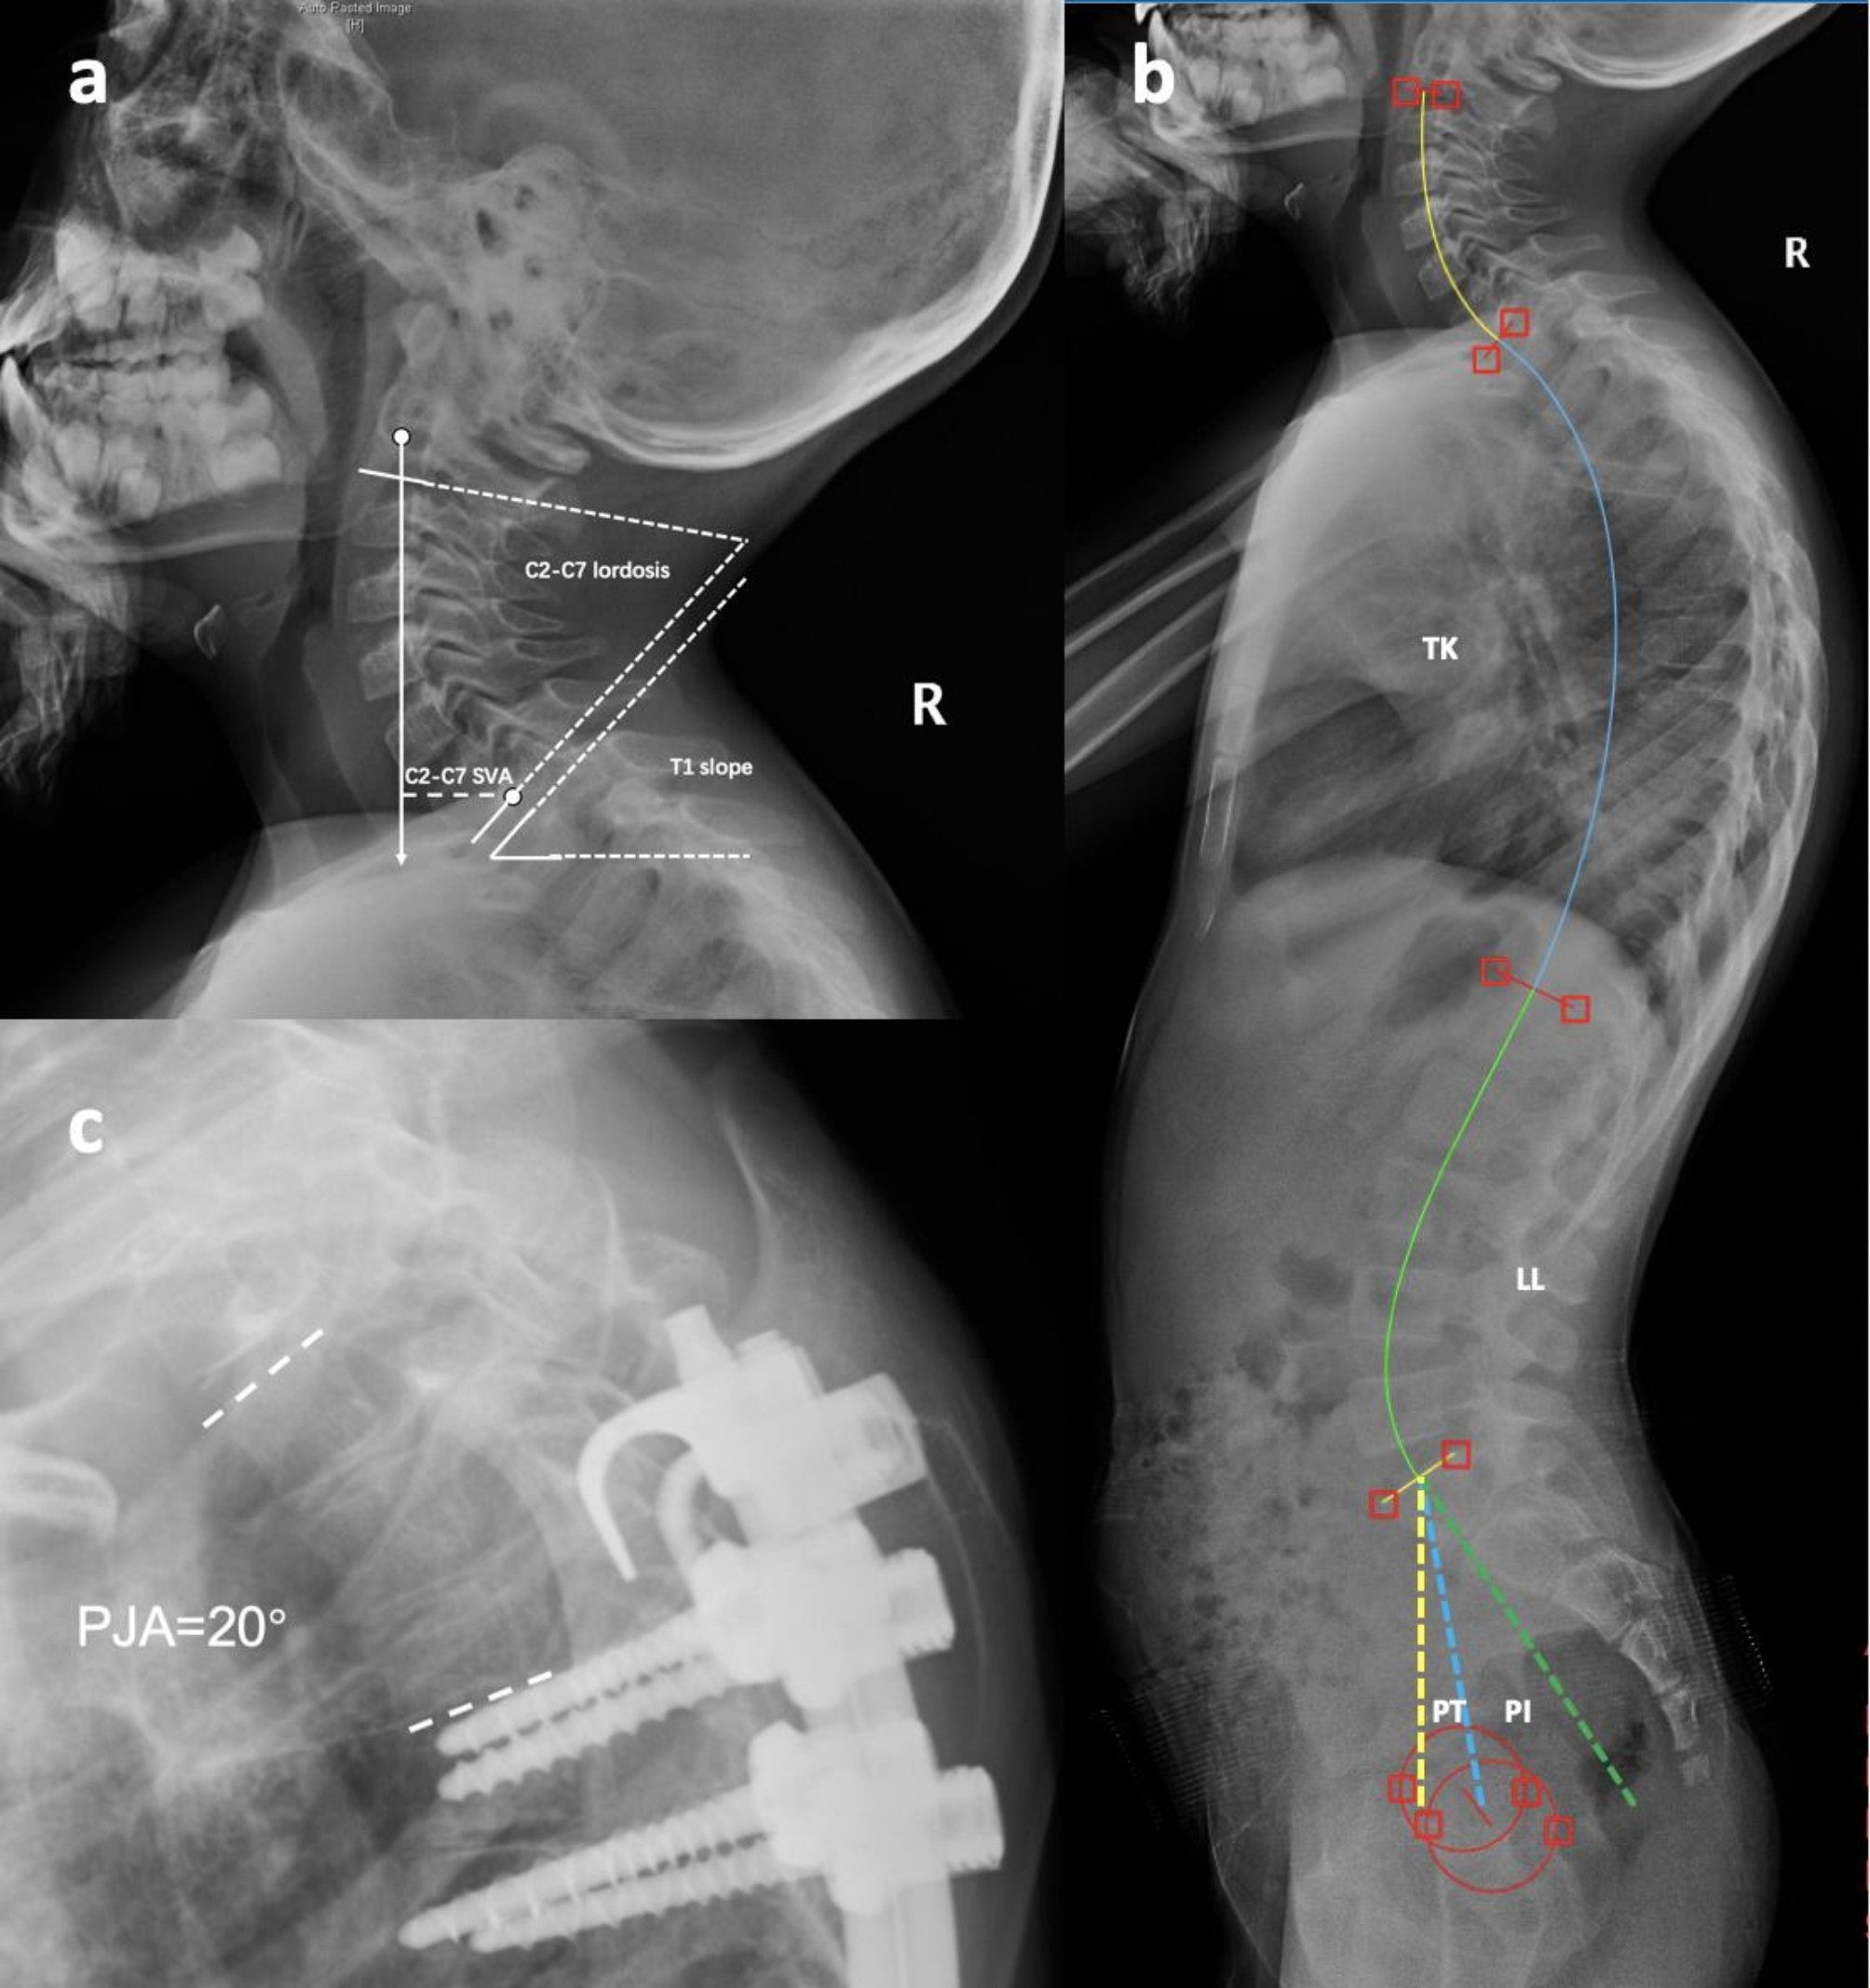

Fig. 1

The measurement demonstration of C2-C7 lordosis, T1 slope and C2-C7 sagittal vertical axis distance (a), thoracic kyphosis (TK), lumbar lordosis (LL), pelvic incidence (PI, angle between the green and blue dotted lines) and pelvic tilt (PT, angle between the yellow and blue dotted lines) (b). Proximal junctional angle (PJA) is defined as the sagittal Cobb angle between the upper instrumented vertebrae (UIV) and the 2nd vertebrae above the UIV (c).